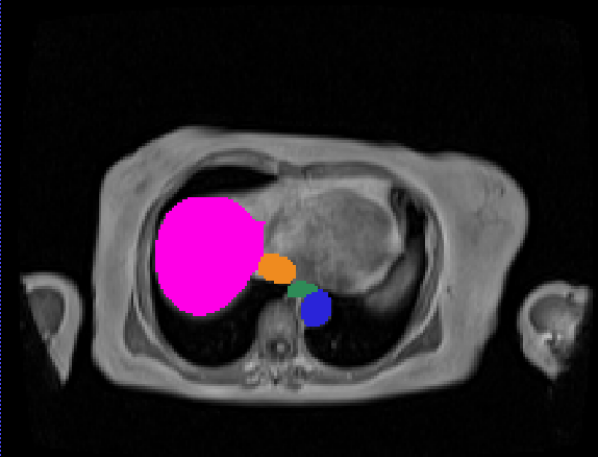

\captionof

figureUKBOB Size and Diversity. Our proposed UK Biobank Organs and Bones (UKBOB) is the largest labeled medical imaging dataset for segmentation, comprising body organs of 51,761 MRI 3D samples (17.9 M 2D images) and a total of more than 1.37 billion 2D masks of 72 organs. Left: we show label examples from UKBOB from axial, coronal, and sagittal views. Right: We show a plot of the size (number of 2D images) and diversity (number of classes) of our UKBOB compared to other medical images datasets. The size of the bubbles indicates 2D image resolution. This new scale in dataset size and diversity should unlock a new wave of applications and methods in the computer vision and medical imaging communities.